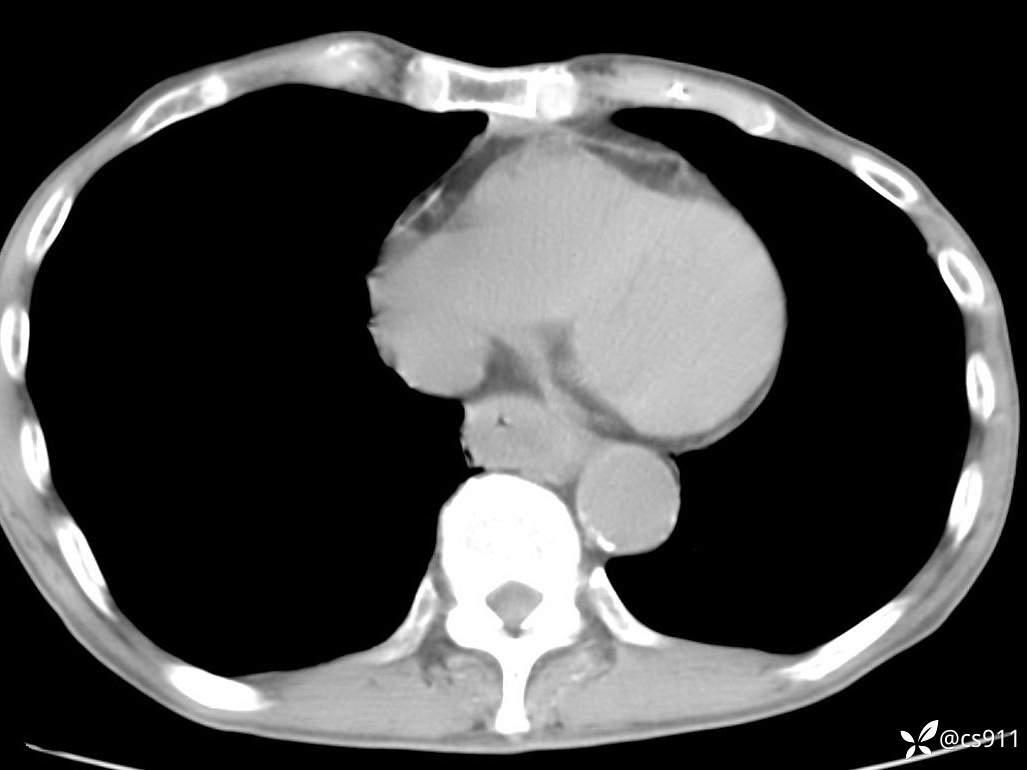

急腹症之急诊CT,原因?答案公布

男,77岁,腹痛、腹胀伴恶心呕吐1天。呕吐胃内容物,非喷射性呕吐,有咖啡色样胃内容物,诉有胃穿孔病史。查体:全腹平,下腹部压痛,全腹无反跳痛,叩诊呈浊音,移动性浊音阴性,肠鸣音减弱,1-2次/分。肛检:直肠未扪及明显肿物,可触及大量粪块。

血淀粉酶(AMY) HH 1859 U/L 35-135